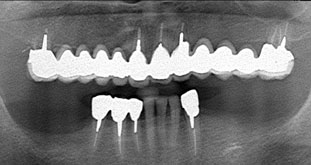

Yさんはバネがかかっている歯を守るために、インプラント治療を選びました。入れ歯の4本の部分にインプラントを入れたのでした。

Yさんはバネがかかっている歯を守るために、インプラント治療を選びました。入れ歯の4本の部分にインプラントを入れたのでした。